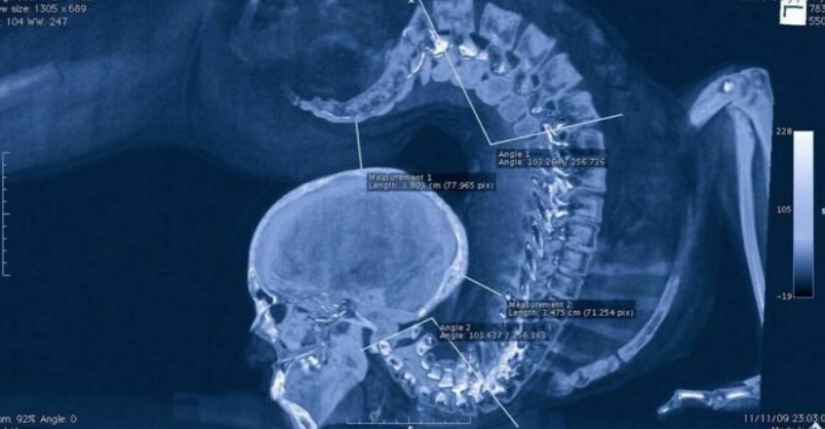

Una radiografía aterradora de una gimnasta realizando un ejercicio